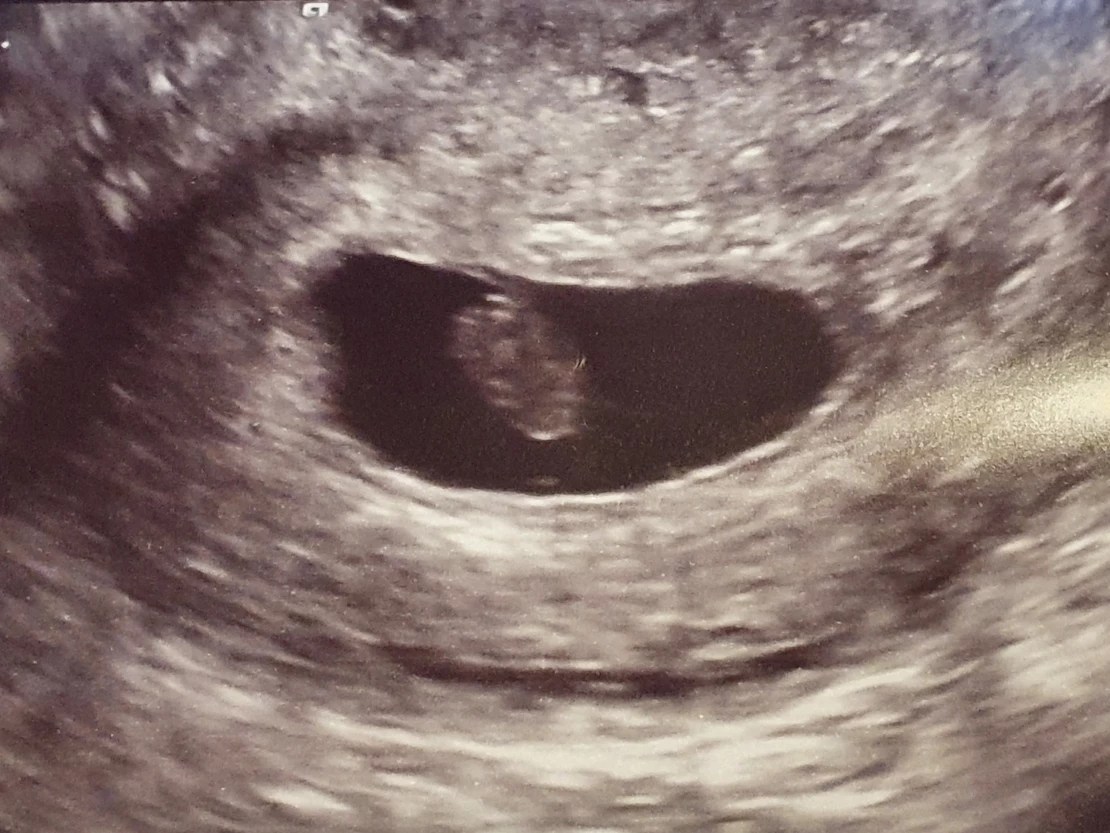

This time my wife was very brave and asked if we could keep a picture of the scan as we hadn’t been given a copy at the private scan on Friday. They did that for us straight away and asked us to keep it hidden whilst we were on the ward. It was back to the internal waiting room for my wife and back out to the corridor for me whilst we waited for a nurse to take us through what happened next.

It may sound strange wanting a scan photo but it helped us with closure. To us this was real, it was our baby. He or she won’t make it to term but for at least seven weeks he or she was growing inside my wife and we don’t want to forget him or her.

I could see on the screen a definite blob but she explained it had no heart beat. Within seconds we had gone from excitement to shock.

They took us to a separate room and gave us a report but there was no photo of our baby to look at. They read through everything. It was 1.55 cm, which was slightly smaller than it should have been but only a week out.